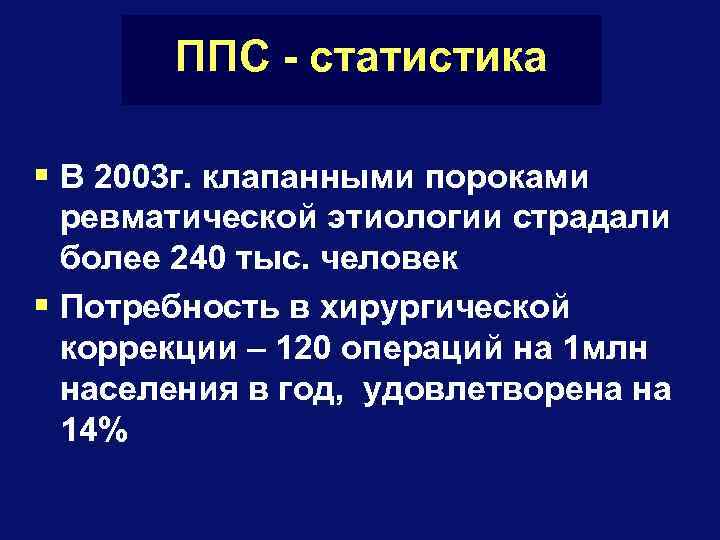

ППС - статистика § В 2003 г. клапанными пороками ревматической этиологии страдали более 240 тыс. человек § Потребность в хирургической коррекции – 120 операций на 1 млн населения в год, удовлетворена на 14%